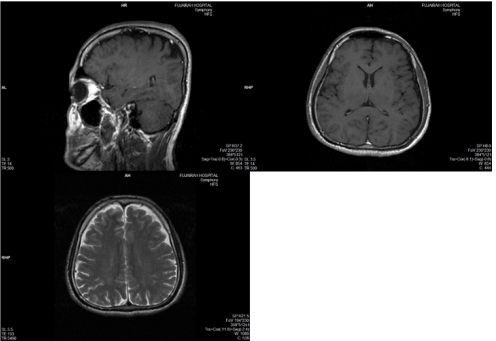

MRI of Head Nov. 01

1. A large pituitary tumor measuring 26x22mm isointense with brain, showing suprasellar extension, it shows calcifications and peripheral enhancement.

2. Brain, ventricles, & cisterns are normal, there is no shift of midline structures…

3. Conclusion: Pituitary Adenoma with suprasellar Extension.

A well-circumscribed mass is present within the expanded sellaturcica. This mass has suprasellar extension and demonstrates iso-intense signal on T1 weighted imaging, heterogeneous but predominantly low signal on T2 weighted imaging, and has predominantly peripheral enhancement, the lesion mildly bulges into the right cavernous sinus with no definite invasion. The optic chiasm is superiorly displaced by the mass and drapes over it. The lesion elevates anterior aspect of floor of the third ventricle without causing hydrocephalus.